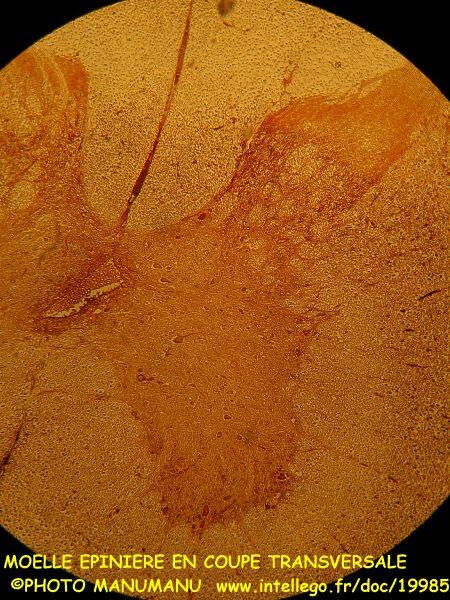

La moelle épinière de Mammifère (Chat) permet facilement d'observer la structure de ce centre nerveux et des neurones qu'elle contient :

on voit bien sur cette coupe transversale au faible grossissement (x40) les méninges, les cornes postérieures/supérieures et les cornes antérieures/inférieures de la substance grise enveloppée dans la substance blanche, le canal central de l'épendyme qui véhicule le liquide céphalorachidien